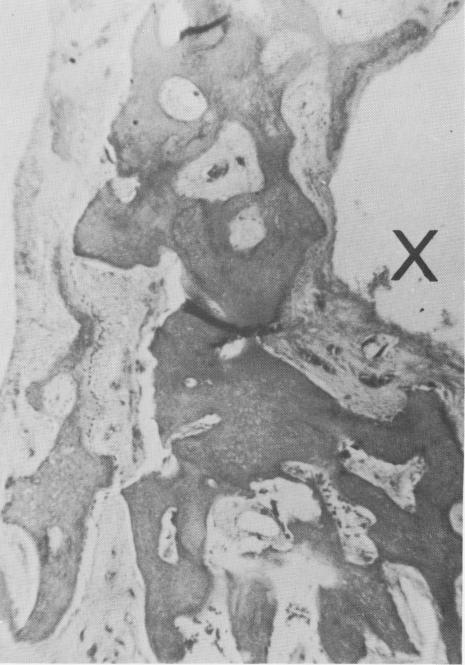

Fig. 4-75. A magnification of the bridge, showing bone covered by a fibrous tissue membrane. X, Implant site. (Courtesy M. Hodosh.)

1 Bony bridge covered by fibrous tissue at crystalline implant site